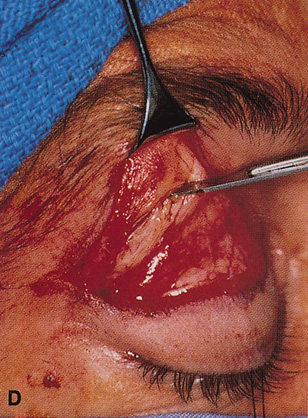

Fig. 11. A. Lateral canthotomy incision is made with straight iris scissors. B. Periosteum is elevated off of the lateral orbital rim. C. Wide undermining allows retraction of the skin incision to permit superior

and inferior osteotomies to be made with the air-driven saw. D. The bony rim has been outfractured. Because of the distensibility of the

skin, it is possible to remove a large bone flap through the small

canthotomy incision. E. The intraconal mass is extracted with the aid of the cryoprobe. F. The bone fragment is positioned for resuturing.

Fig. 11. A. Lateral canthotomy incision is made with straight iris scissors. B. Periosteum is elevated off of the lateral orbital rim. C. Wide undermining allows retraction of the skin incision to permit superior

and inferior osteotomies to be made with the air-driven saw. D. The bony rim has been outfractured. Because of the distensibility of the

skin, it is possible to remove a large bone flap through the small

canthotomy incision. E. The intraconal mass is extracted with the aid of the cryoprobe. F. The bone fragment is positioned for resuturing.

|